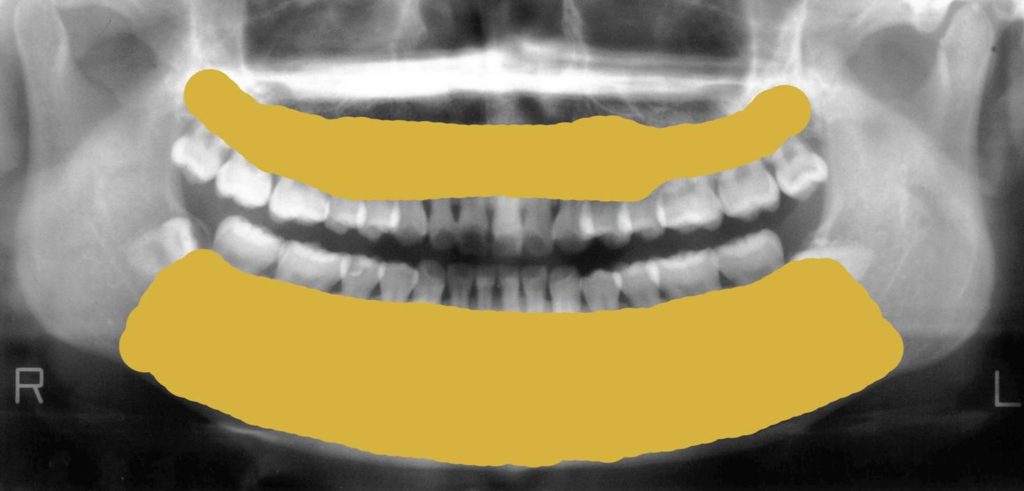

次の写真は歯科レントゲンで見る下顎の骨です。

赤く線を引いている部分が下の顎の骨部分になります。

硬い部分が白くうつります。

硬い部分とは骨です。

歯科レントゲンで見る上顎(あご)の骨

次に上の顎の骨をみていきましょう。

青い線の上側が上の顎の骨部分になります。

下図のように骨がしっかりある方もいらっしゃいます。元々はみなさん骨があったはずです。

歯周病やなんらかの理由で次の図のように歯が溶けて少なくなっている方もいらっしゃいます。

歯を支えている骨部分がもともとはこれだけの量があります。

しかし骨が少なくなるとこんな風になってしまうのです。